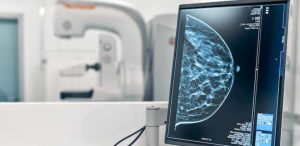

Mamografia Digital: detecção precoce e principais vantagens

Sabe-se que a mamografia digital é um exame indicado para diagnosticar o câncer de mama. O câncer de mama é uma doença que acomete cerca